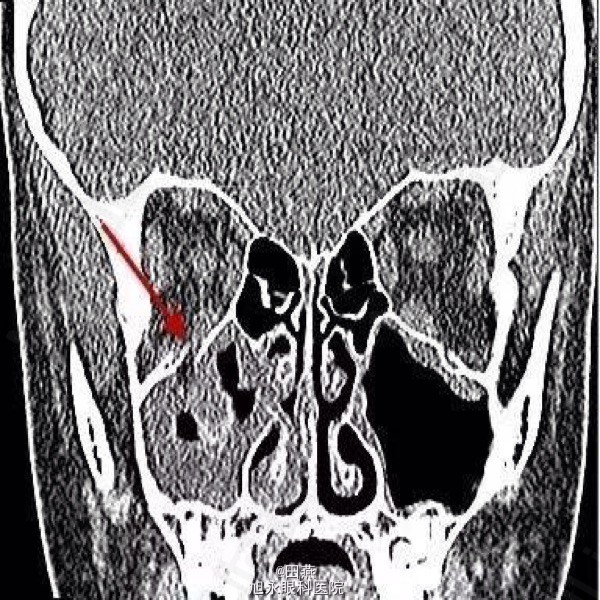

患眼视力1.0,有-4的眼球上转不足,-2的下转不足。第一眼位(见下图)右眼眼压13mmHg,上视时增加为23mmHg。颌面部CT显示右眼眶底轻微骨折

诊断:眼眶活板门样骨折致下直肌嵌顿 处理:释放嵌顿组织,骨折处植入人造眼眶底板